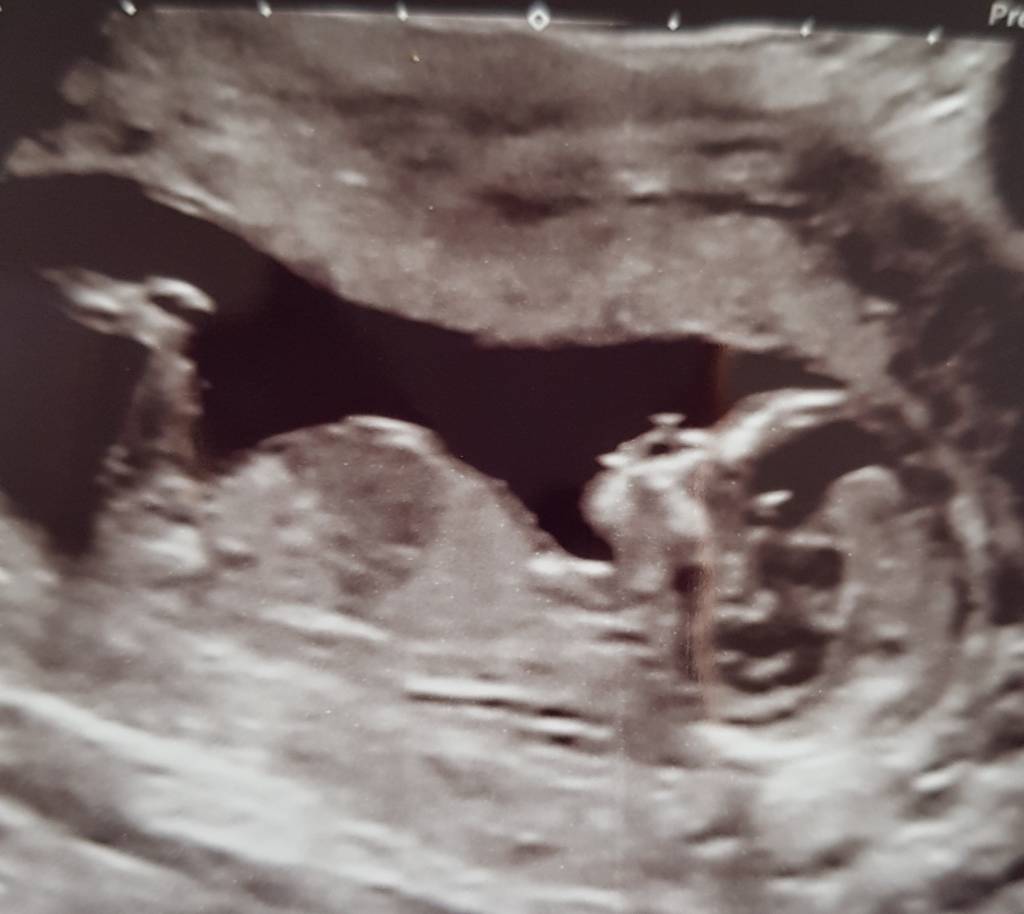

Hi as you can tell I'm ridiculously impatient. I am so eager to find out if I'm having a boy or a girl I've been looking up theories. Looking at the symptoms I've had it edges towards a boy but im assuming those are just old wives tales. The most positive one seems to be the nub theory however I can't seem to see one on ours. This scan as do e at 12 weeks 5 days. Does anyone have any idea on the gender or nub theory? :)Attachment 37902